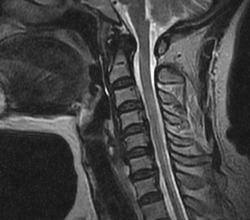

頚椎椎間板ヘルニアは、首の背骨の頚椎と頚椎の間にあるクッションの役割を果たす「椎間板」が加齢、過度の負荷、外傷などによって後方に飛び出すことによって起こります。

飛び出したヘルニア部分が神経根や脊髄を圧迫することで、痛み、しびれ、知覚鈍麻、筋力低下などを引き起こします。

頚椎椎間板ヘルニアの症状は大きく分けて、神経根のみの圧迫症状の「神経根症状型」、脊髄の圧迫症状のある「脊髄症型」、この二つを併せ持つ「脊髄神経根型」があります。以下の症状は首を後ろに倒したときに増強し、普段の姿勢やスポーツの時にも注意が必要になってきます。